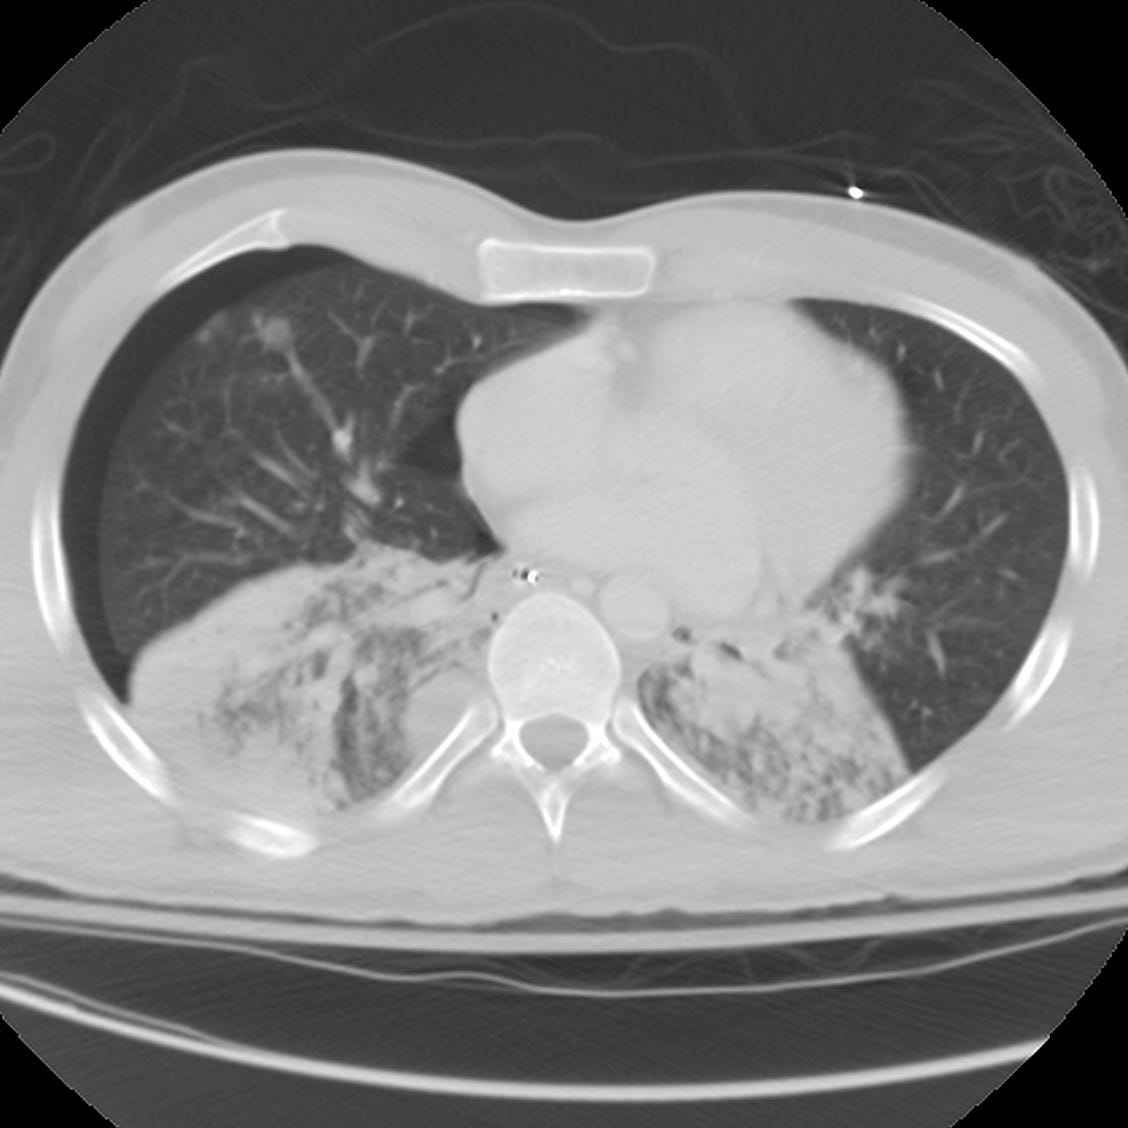

QuizWhat is the most likely etiology of these lower lobe pulmonary opacities?ChestAlexander BaxterMay 11, 20232ShareFor discussion click here.PreviousNext